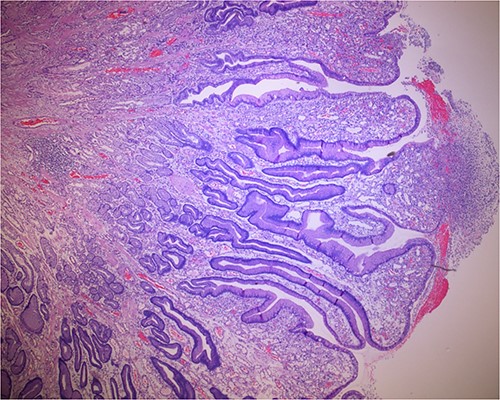

Histologic sections of the polyps demonstrated benign gastric hyperplastic polyps with acute and chronic gastritis (Fig. 2). Portions of the gastric polyps and adjacent mucosa were covered by inflammatory cell exudate (Fig. 3). Higher magnification revealed conspicuous volcanic-like eruption of the exudate, reminiscent of pseudomembranous gastritis (Fig. 4). Alcian yellow and GMS stains were negative for Helicobacter pylori and fungal organisms, respectively.

Volcanic-like eruption of inflammatory exudate, reminiscent of pseudomembranous gastritis.